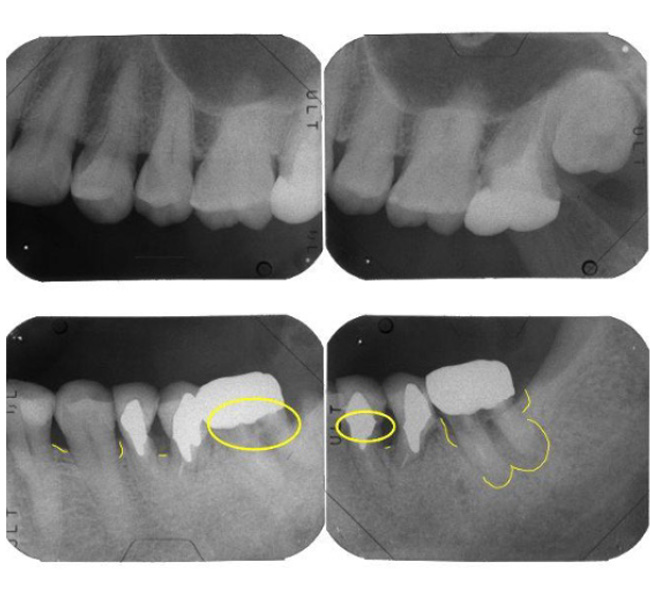

【レントゲン】左下奥歯のレントゲン所見

一番奥の歯(左下7番)は、被せ物の下の土台にヒビ(破折)が入っており、歯の内部と外部の両方から細菌感染が進んでいる「末期的な状態」です。周囲の骨が広範囲に溶け、大きな黒い影として写っています。

その手前の歯(左下6番)は、過去に根を分割する処置がされていますが、土台が根の方向からズレており、噛み合わせの強い力に耐えきれず地盤(骨)を半分以上失っています。

どちらの歯も、これ以上の補修では建物の重み(噛み合わせの力)を支えられず、放置すれば周囲の健康な骨までさらに溶かしてしまうため、将来を見据えて「戦略的な抜歯」を選択しました。

患者さんの継続的な努力により、お口全体の細菌のコントロール(プラークコントロール)は劇的に改善しました。しかし、左下奥歯(6・7番)には依然として4〜7mmの深い歯周ポケットと炎症が残存しています。

これは、たとえ表面の細菌を取り除いても、歯の内部に「ヒビ(破折)」や「エンドペリオ(神経と歯周病が繋がった病変)」という構造的な欠陥がある場合、そこを温床とする細菌を完全に排除することが不可能なためです。このデータに基づき、周囲の健全な骨をこれ以上破壊させないための「戦略的な抜歯」を最終決定しました。

抜歯から1年半後の経過

抜歯と同時に行った「リッジプリザベーション(歯槽骨保存術)」により、建物の土台となる地盤(歯槽骨)が理想的な形で維持されています。通常、抜歯後は地盤沈下のように骨が痩せてしまいますが、適切な処置によって吸収は認められません。

この期間、他の部位の「基本治療」も着実に進行しました。隣の歯(左下5番)には、精密なプレスセラミックによる新しい修復を施行。以前の暫定的な詰め物(CR修復)では対応しきれなかった複雑な形態も、高い適合精度で再構築され、細菌の侵入を許さない強固な構造へと生まれ変わっています。